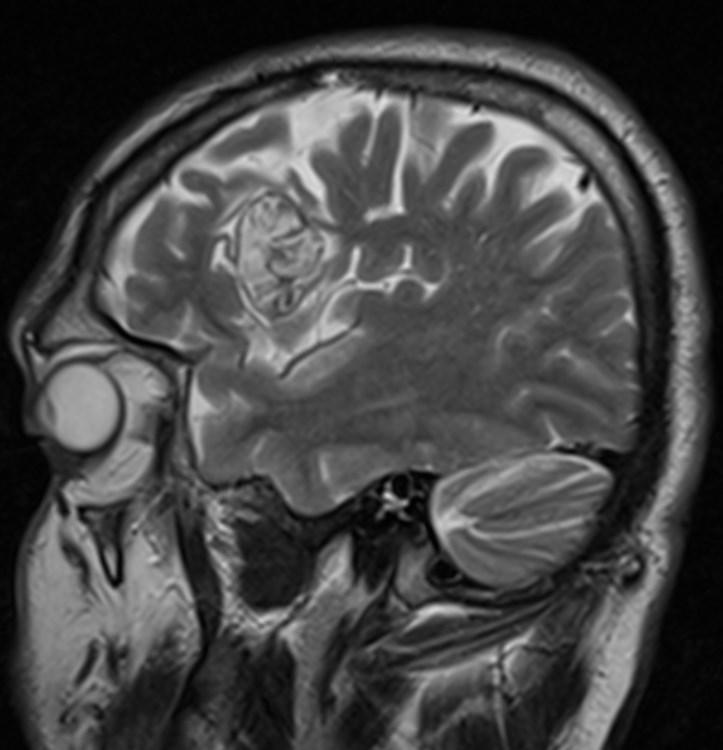

Answer: Primary hydatid cyst of right frontal lobe.

MR images revealed Gharbi type V hydatid cysts in right frontal lobe.

Gharbi classified hydatid cyst ultrasonographic images into 5 types: Type 1, walled, unilocular, anechoic; type 2, separated membranes; type 3, multisepta, daughter vesicles; type 4, heterogenic, hypo-hyperechogenic; type 5, calcification of a section of the wall or completely calcified (4). The cysts characteristically have three components: Pericyst, Exocyst, and Endocyst.